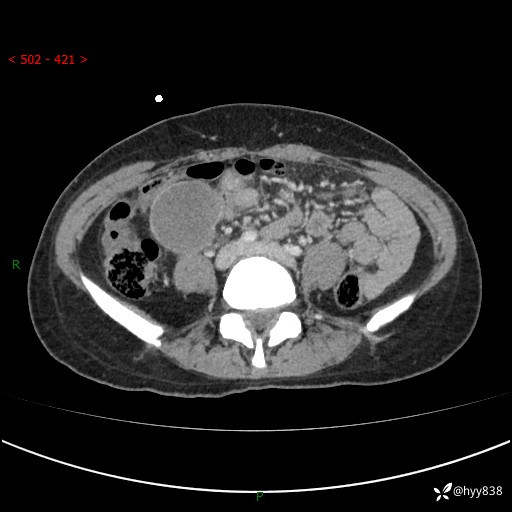

年轻女性,发现腹腔肿物1周。圆圆的肿物,诊断有难度---结果公布~

主诉:发现腹腔肿物1周

现病史:患者自诉于1周前无明显诱因出现剑突下间断性隐痛,尚可忍受,不向其它部位放射,无恶心呕吐、腹泻便秘等不适,于当地市第二人民医院就诊,行CT结果示:1.右中腹占位,间叶组织来源可能2.小肠梗阻3.盆腔积液4.腹腔积液5.副脾6.肝囊肿;于荆州二医行抗炎,抑酸,护胃,补液等对症支持治疗;患者病情好转,今为求进一步诊治,遂来我院门诊就诊,门诊以“腹腔肿瘤”收入院。 起病以来,患者精神、睡眠、饮食一般,大小便正常,近期体力体重无明显改变。

腹部CT增强(外院平扫)